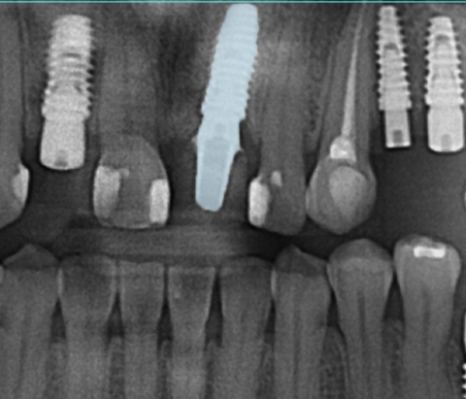

마무리 된 사진

함께 보도록 하겠습니다.

🔽

위 사진은 임플란트 수술까지

마무리가 된 사진인데요.

개인의 잇몸상태를 분석하여

식립각도와 위치를 신경써서

안정적인 임플란트를 심어드렸고

반영구적으로 사용할 수 있도록

도와드렸습니다.